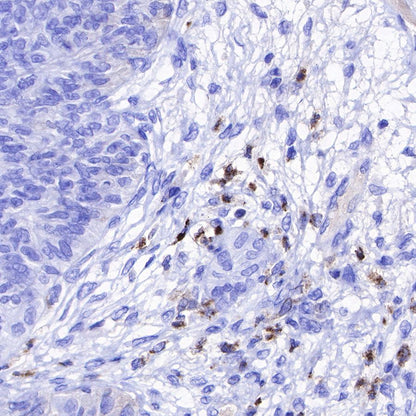

Immunohistochemistry

IHC shows positive staining in paraffin-embedded human tonsil. Anti-Lysozyme antibody was used at 1/100 dilution, followed by a HRP Polymer for Mouse & Rabbit IgG (ready to use). Counterstained with hematoxylin. Heat mediated antigen retrieval with Tris/EDTA buffer pH9.0 was performed before commencing with IHC staining protocol.

IHC shows positive staining in paraffin-embedded human spleen. Anti-Lysozyme antibody was used at 1/100 dilution, followed by a HRP Polymer for Mouse & Rabbit IgG (ready to use). Counterstained with hematoxylin. Heat mediated antigen retrieval with Tris/EDTA buffer pH9.0 was performed before commencing with IHC staining protocol.